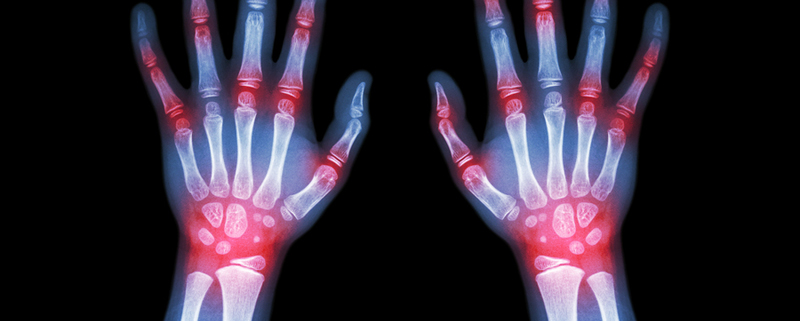

A systemic disease is a disease that affects other parts of the body, or even the whole body. The hands are complex. They are composed of many types of tissue including blood vessels, nerves, skin and skin-related tissues, bones, and muscles/tendons/ligaments. Because of this complexity, the hands may suffer from side effects of systemic diseases. Here are some examples that may affect the hand:

1. Arthritic Swelling: Swelling of the middle joint of a finger is called a Bouchard’s node, and swelling at the small finger joints are called Heberden’s nodes.